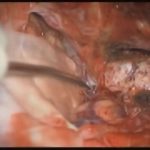

術中写真

摘出 中